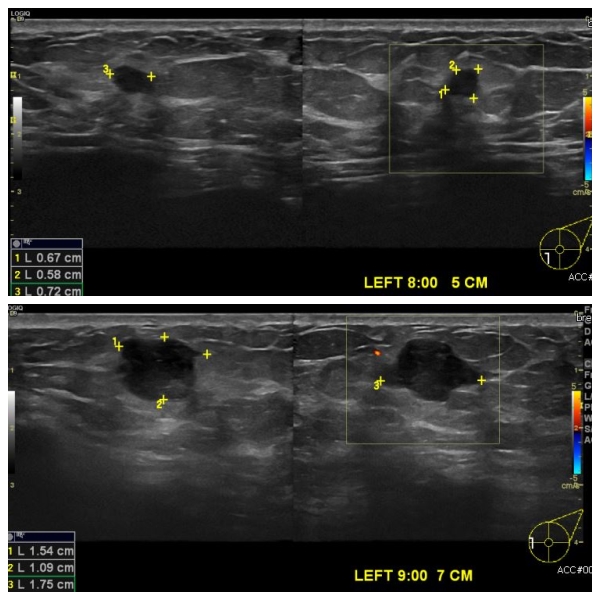

상기환자 검진상 이상 소견으로 내원하신 40대 여성 분으로  유방초음파상

좌측 9시 7cm 떨어진 거리의 의심스러운 혹  조직검사 시행하여  좌측 침윤성유관암

진단되었습니다.